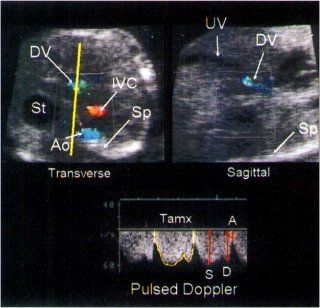

The ductus venosus is located at the cephalic end of the intra-abdominal portion of the umbilical vein. Since the ductus venosus is a small vessel measuring only a few millimeters in diameter, it is often difficult to visualize with real-time ultrasound. However, color Doppler ultrasound enables the examiner to rapidly and accurately identify this vessel. The reason for this is because flow through the ductus venosus is accelerated, and, as a consequence of its small size, turbulent. Identification of the ductus venosus can be accomplished using two approaches. First, the examiner directs the ultrasound beam transversely through the fetal abdomen at the level of the stomach. After activating the color Doppler using a low velocity setting (<0.24 m/s), three vessels can be imaged in cross-section: the abdominal aorta, the inferior vena, and the ductus venosus

In this view the ductus venosus is located to the right of the stomach, in a plane anterior to the abdominal aorta. Because of turbulent flow, the ductus venosus often has a ‘sparkling’ appearance which is the result of aliasing. Once the ductus venosus is identified, the transducer beam is rotated 90o to image the long axis of this vessel which allows the examiner to adjust the angle of the pulsed Doppler sample volume for angle-dependent measurements

In 1992 Kiserud and colleagues reported results from examination of 29 normal fetuses and found that the Tamx of the waveform and the peak velocity of at the (A) wave increased linearly with gestational age 25. In 1992, Huisman et al performed a cross-sectional study of 60 fetuses between 19 and 39 weeks of gestation and divided them into three groups: 19-22 weeks, 27-30 weeks, and 36 to 39 weeks 26. They found that the Tamx and the peak velocity of the peak systolic velocity (S) and the peak diastolic (D) waves increased with gestational age, but made no mention of changes in the A wave peak velocity. Huisman and colleagues reported that the ductus venosus had a higher peak velocity (40-80 cm/s) than other venous vessels (inferior vena cava, right hepatic vein and umbilical vein) 26. In 1994, Hecher and colleagues reported results from a cross-sectional study of 134 normal fetuses. The Tamx, S and D peak velocities increased from 18 to 30 weeks did not change from 30 to 34 weeks and then decreased from 34 to 40 weeks. The A wave demonstrated an increase in velocity until 34 weeks, following which it did not increase 24.